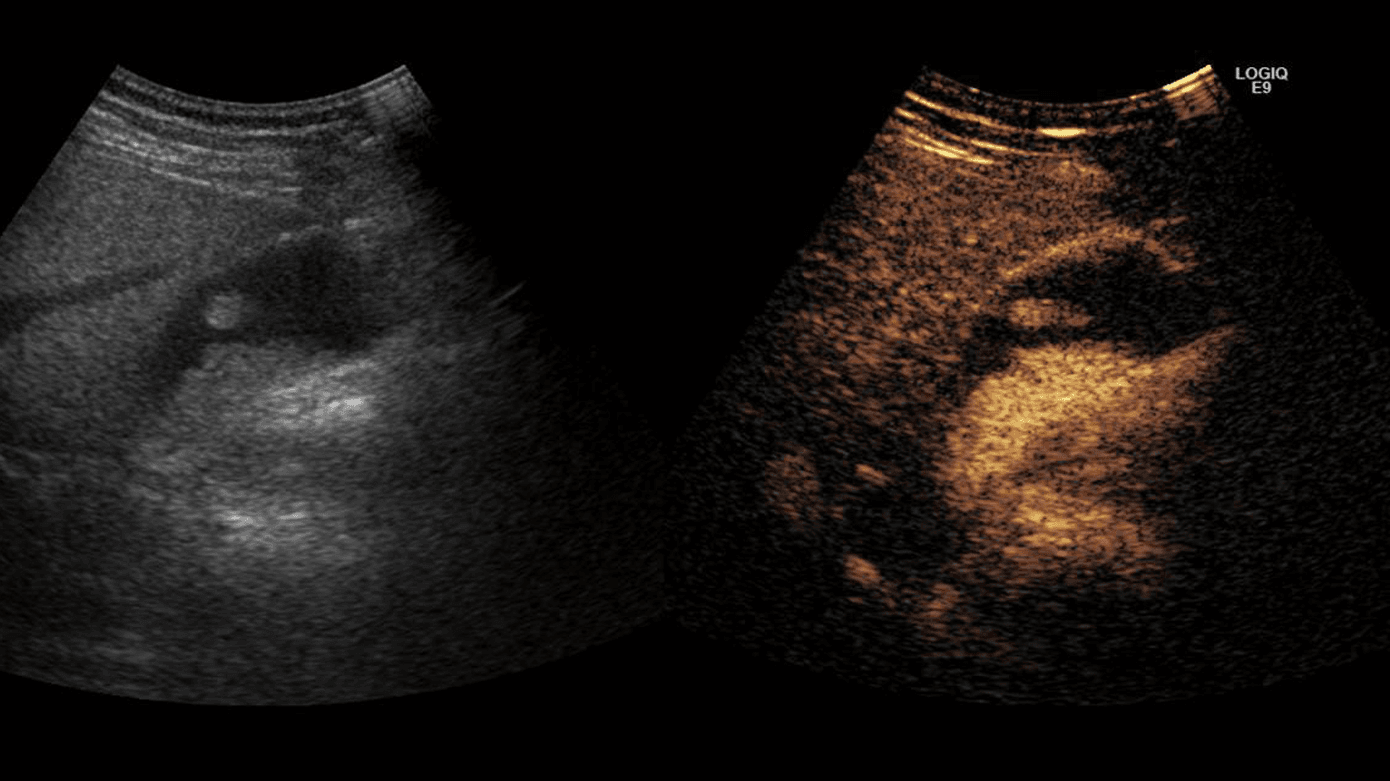

UL-skanning er den foretrukne undersøgelse til diagnostik og kontrol af GBP med en sensitivitet og specificitet på henholdsvis 83% og 96% for ægte polypper [11]. Endoskopisk UL (EUL)-skanning og UL-skanning med kontrast (CEUS) anbefales ikke rutinemæssigt, men kan eventuelt overvejes til at støtte beslutningstagningen i tvivlstilfælde [2, 4]. EUL-skanning har den højeste sensitivitet [2, 12]. CEUS- og Color-Dopplerskanning (CDI) visualiserer kar og kan i nogle tilfælde bidrage med hjælp til at skelne sludge og småsten i galdeblæren fra neoplasi [13]. CT og MR-skanning har ingen plads i forhold til diagnostik af GBP, men CT og PET-CT anvendes til stadieinddeling af GBC [2].

Risikofaktorer for GBC ved UL-skanning er solitære polypper, størrelse > 10 mm, sessil (bredbaset) form, samtidig lokalfortykkelse af galdeblærevæggen > 4 mm og/eller opbrydning af den normale lagdeling af galdeblærevæggen (Figur 2). Ved brug af CEUS-skanning og/eller CDI kan øget vaskularisering bestyrke mistanke om malignitet, men ikke bidrage med definitiv diagnose [2] (Figur 2).

Der eksisterer ikke specifikke malignitetskriterier, men som malignitetskarakteristika ud over størrelse > 10 mm ved UL-skanning kan anvendes sessil polyp, og der er basis for yderligere mistanke ved fokal opbrydning af galdeblæren, lagdeling eller lokaliseret vægfortykkelse > 4 mm. WFUMB nævner desuden, at solitær polyp og øget vaskularisering ved CEUS-skanning og/eller CDI har været anvendt som indikator for mulig øget risiko, men dette er ikke evidensbaseret.

Der er enighed om sessil form af GBP associeret med ændret vægstruktur og lokaliseret galdeblærevæg > 4 mm som risikofaktor ved UL-skanning. Anbefalingerne fra Wiles et al inkluderer aktuelt ikke solitære polypper som risikofaktor for GBC, men understreger, at dette fund med samtidig forekomst af øvrige risikofaktorer for GBC bør øge mistanken. WFUMB inkluderer denne parameter som risikofaktor ved UL-skanning og foreslår eventuelt at inddrage brug af CEUS-skanning og/eller CDI i den samlede vurdering i tvivlstilfælde.